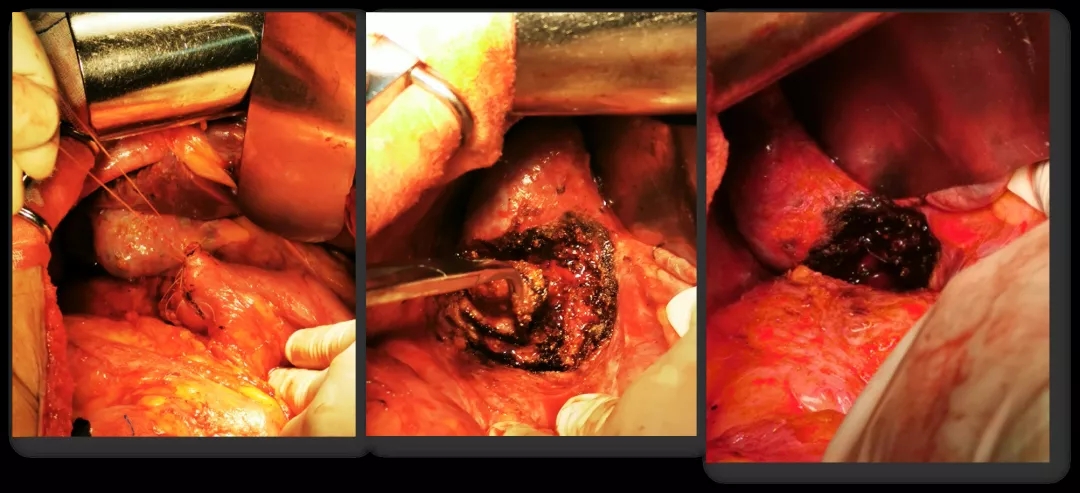

2016.10.26行三次减瘤术(乙状结肠部分切除侧侧吻合+腹盆腔减瘤+腹膜后淋巴结切除),术后无肉眼残留。

术中所见